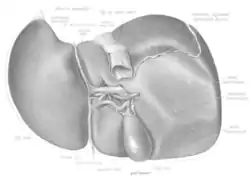

Visceral surface of the liver showing the four lobes | |

In anatomy, a lobe is a clear anatomical division or extension[1] of an organ (as seen for example in the brain, lung, liver, or kidney) that can be determined without the use of a microscope at the gross anatomy level. This is in contrast to the much smaller lobule, which is a clear division only visible under the microscope.[2]

- The four lobes of the liver